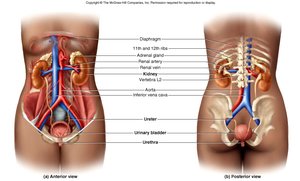

The urinary system is essential for maintaining homeostasis by filtering blood, removing waste, and regulating fluid and electrolyte balance. It consists of the kidneys, ureters, urinary bladder, and urethra.

The kidneys are retroperitoneal organs located in the abdominal cavity, protected by connective tissue and adipose layers. Each kidney contains about 1.2 million nephrons, the functional units responsible for urine formation.

Blood Supply: Kidneys are highly vascularized, receiving about 20% of cardiac output.